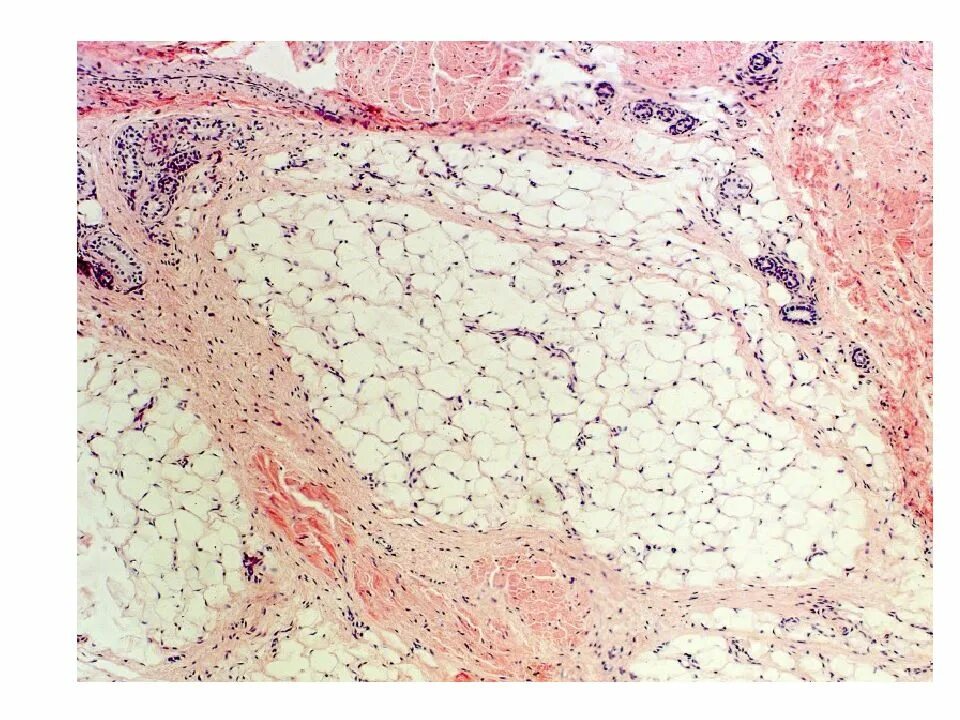

Гистологические препараты соединительная ткань